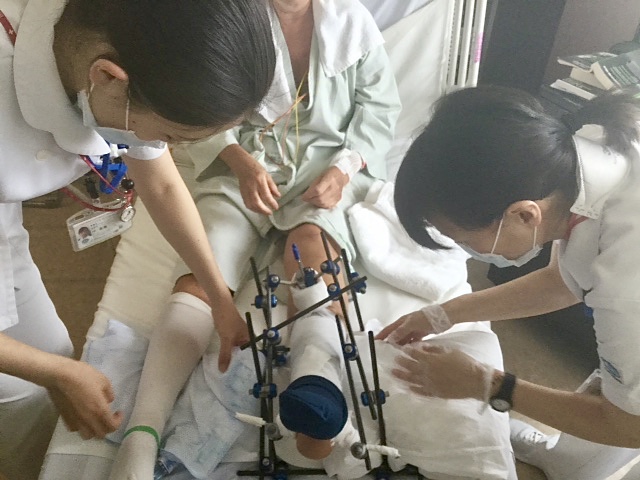

La fracture, le fixateur externe, la vue de sa chambre au 14-ème, mon hôtel, ma chambre (aux dimensions plus que modestes) et mon 7/11 juste en face.

Opération fixée au 25 juin. Avant et au réveil (l’opération aura duré un peu plus de 5 heures, il s’est agi de reconstituer et remettre ensemble, selon les mots du chirurgien, les pièces du puzzle).

Le chirurgien et le personnel médical.

Au final Alexandra a été très bien soignée (le chirurgien a fait un excellent travail aux dires de ses collègues français vus après), très bien traitée (pour les repas entre autres même si à la fin elle n’en pouvait plus du riz), les infirmières ont été très attentionnées, IMA prenant régulièrement de ses nouvelles, jusqu’au jour où elle a été jugée « fit to fly ». Rapatriement du National Center for Global Health & Medicine de Tokyo-Shinjuku au 993, avenue de la République à Marcq dans d’excellentes conditions., nous avons tenu à exprimer notre gratitude à tous ceux qui nous ont aidés et soutenus, et surtout la MAIF par l’entremise d’Inter-Mutuelles-Assistance.